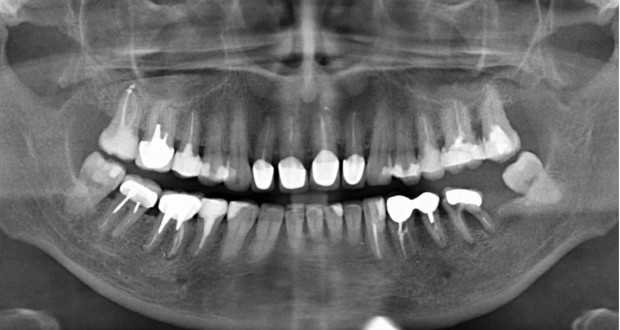

Панорамный рентген зубов

Панорамный рентген, или ортопантомограмма, — это высокоинформативный способ увидеть всю систему зубов. Снимок охватывает не только зубные ряды, но и суставы, носовые пазухи и окружающие мягкие ткани. Благодаря этому стоматолог может выявить скрытые патологии, определить оптимальную стратегию лечения и избежать возможных осложнений.

• Диагностика заболеваний — с помощью панорамного рентгена можно обнаружить кисты, гранулемы, новообразования, воспалительные процессы в костной ткани и скрытые очаги инфекции.

• Обнаружение скрытого кариеса — стандартный осмотр не всегда позволяет выявить пораженные участки между зубами и под пломбами, а ортопантомограмма помогает это сделать.